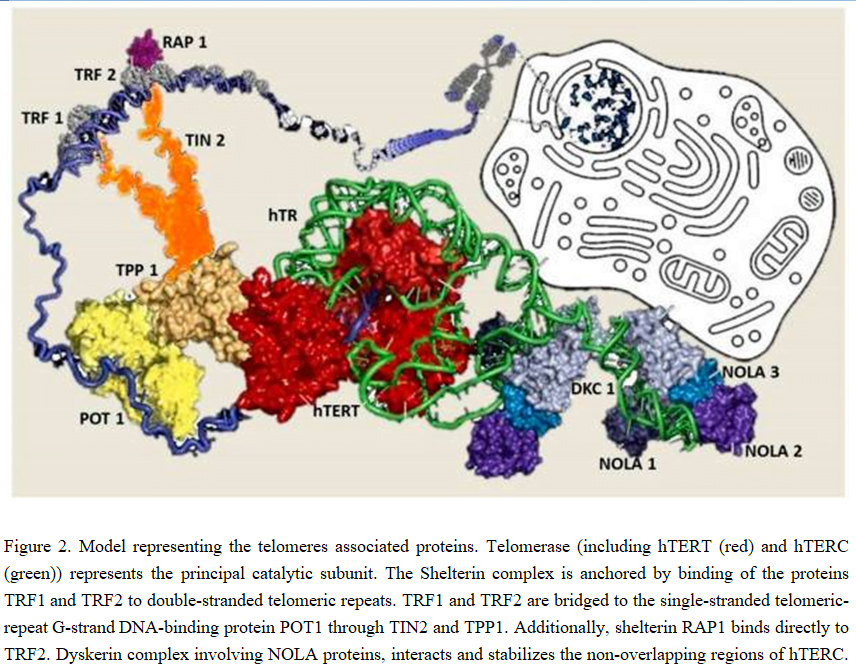

In humans, telomeres consist of thousands copies of six base repeats (TTAGGG) located at the extremities of the chromosomes that protect chromosomes tips from end-to-end fusion, rearrangement and translocation. Telomere length is progressively shortened at each mitosis, due to the inability of the DNA polymerase complex to replicate the very 5′ end of the lagging strand (attrition). For this reason, telomere shortening may function as a “mitotic clock” to sense somatic cells aging. When telomeres become critically short, a DNA-damage program is activated, leading to apoptosis or cell senescence. On the contrary, immortal cells (cancer, stem and germ cells) constitutionally express telomerase, a ribonuclear enzymatic complex associated with telomeres that is responsible for stabilizing telomere length by synthesizing new DNA sequences and adding them to the end of the chromosomes during DNA replication [17]. Telomerase comprises two essential components: Telomerase reverse transcriptase (hTERT) and its RNA template, the telomerase RNA component (hTERC). Dyskerin complex binds to hTERC, in order to protect it and to stabilize the telomerase complex. It includes four nucleolar proteins: Dyskerin (DKC1) and Nucleolar protein family A member 1, 2 and 3 (NOLA1-NOLA2-NOLA3). Besides telomerase, the Shelterin complex, which binds specifically to telomeres, plays a fundamental role in the protection of chromosome ends facilitating telomerase-based telomere elongation. It is composed of six core proteins: the telomeric repeat binding factors 1 and 2 (TRF1-TRF2) that bind telomeric double strand DNA, the protection of telomeres 1 (POT1), which binds the 3′ telomeric region of single strand DNA avoiding the degradation by nuclease, and the TRF-1 interacting protein 2 (TIN2), the POT1-TIN2 organizing protein (TPP1) and the repressor/activator protein 1 (RAP1), that interact with the other proteins bound to telomere stabilizing the complex (Figure 2; [17, 21]). Mutations of proteins involved in maintenance and repair of telomeres are responsible for telomeropathies [19]: a spectrum of progressive genetic diseases exemplified in the most severe cases by dyskeratosis congenita (DKC), whose common autosomal recessive form is caused by mutations in DKC1.